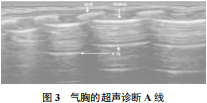

1.1.3 A 线特征

当声束垂直于胸膜时,混响伪影引起的多次反射将产生平行于胸膜线的线性超回声,它位于胸膜线下方。超声下可见一系列平滑、清晰、规则的线性高回声,与胸膜线平行,间隔均匀;从浅肺到深肺,回声逐渐减弱,最后消失。

在遇到胸膜的多次反射后,超声形成的平行于胸膜的多条亮线是一种混响伪影,有助于气胸的诊断,表现为平行于胸膜的高回声水平线,等距、弱信号。每条A线之间的距离表示壁胸膜与皮肤表面之间的距离。A线通常在肺密度正常时出现,在气胸患者中也可以看到,如图3所示。